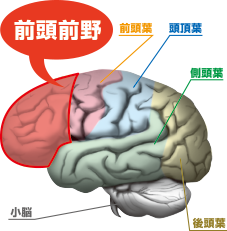

Images Of 前頭前野 Japaneseclass Jp